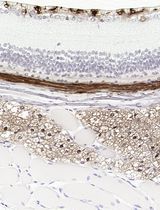

Improved Immunohistochemistry of Mouse Eye Sections Using Davidson's Fixative and Melanin Bleaching